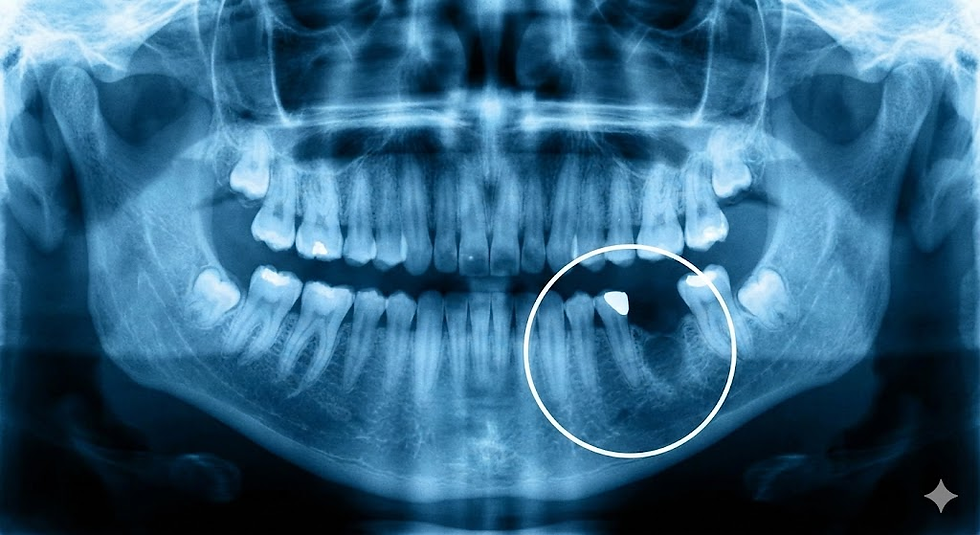

Det hele starter med en grundig forundersøgelse. Vi anvender avanceret 3D-røntgen (CBCT-scanning) for at få et præcist billede af din kæbes nuværende tilstand. Her vurderer vores specialister præcis, hvor meget knogle der mangler, og hvilken metode der er mest optimal for dig.